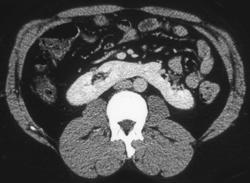

Stones in Distal Ureter